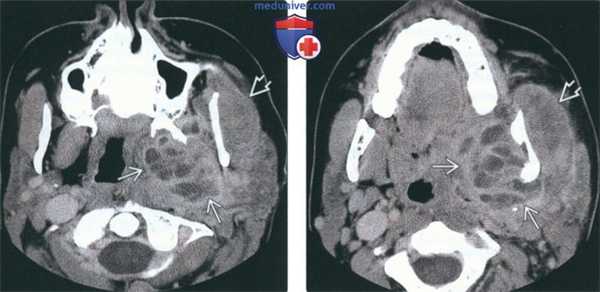

(Слева) На аксиальной КТ с КУ определяется большой многокамерный абсцесс внутреннего ЖП с вовлечением крыловидных мышц. Обратите внимание на утолщение и отек жевательной мышцы в наружном жевательном пространстве. У этого пациента 21 года девять месяцев назад был удален моляр слева, после чего появилась оталгия в сочетании с тризмом, неверно расцененные как проявления синдрома ВНЧС.

(Справа) На аксиальной КТ с КУ у этого же пациента определяется дальнейшее распространение абсцесса внутреннего ЖП в и отек жевательной мышцы.

2. КТ при абсцессе жевательного пространства:

• КТ с КУ:

о Патологический очаг в ЖП со сдавлением окологлоточного пространства в направлении спереди/снаружи-кзади/кнутри

о Очаг жидкостной плотности с толстым контрастирующимся «ободком» в жевательных мышцах = абсцесс ЖП:

- Отек и контрастирование прилежащих мышц без сопутствующей жидкости = миозит

- «Мутные» соседние жировые пластинки = целлюлит

о Линейные уплотнения в подкожной клетчатке и утолщение кожи помогают отличить злокачественную опухоль от инфекции